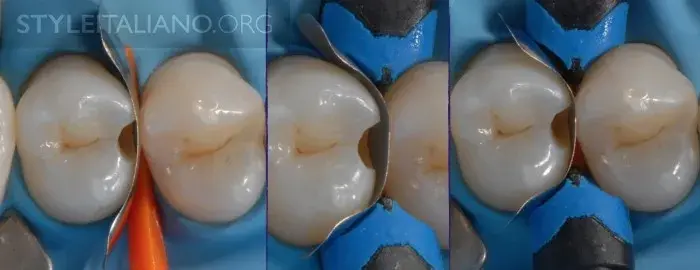

Рис. 10 — Раскрытие полости.

Рис. 11- Раскрытие полости.

Рис. 21 – Клинья для сохранения соседних зубов.

Рис. 22 — Матрица.